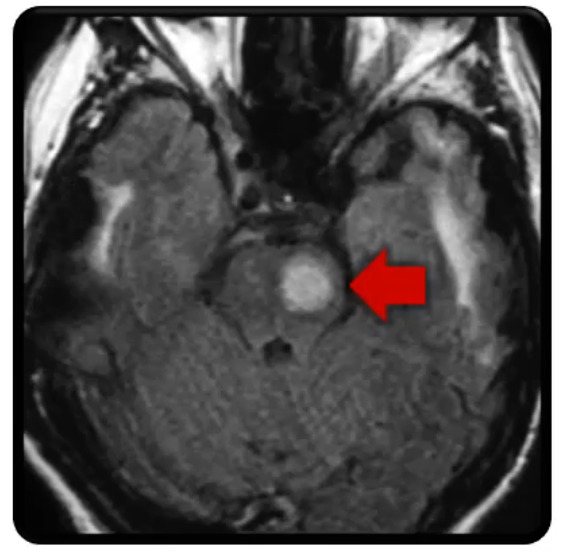

What is the pathology in this radiograph?

ruptured aneurysm

Pontine Stroke